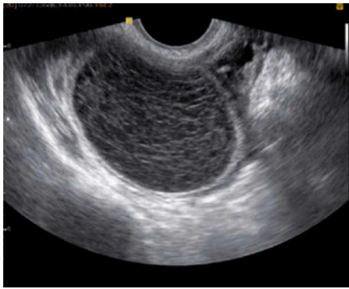

Paciente de 24 anos, comparece ao pronto socorro

com queixa de dor em região suprapúbica e na fossa

ilíaca à direita, com início há cerca de 2 dias e piora

progressiva. Nega queixas urinárias ou

gastrointestinais. Menarca aos 12 anos, sexarca aos

18 anos, vida sexual ativa com parceiro único, com

uso de preservativo masculino. Método

contraceptivo: DIU de cobre. A data da última

menstruação foi há 2 semanas e 5 dias. Ao exame

físico, bom estado geral, estável

hemodinamicamente, mucosas coradas; dor à

palpação profunda da fossa ilíaca direita, sem sinais

de peritonite. Ao toque vaginal, identifica-se massa

palpável na mesma topografia.

A USG-TV veio com o seguinte achado:

Frente a essas informações, qual a melhor hipótese diagnóstica?